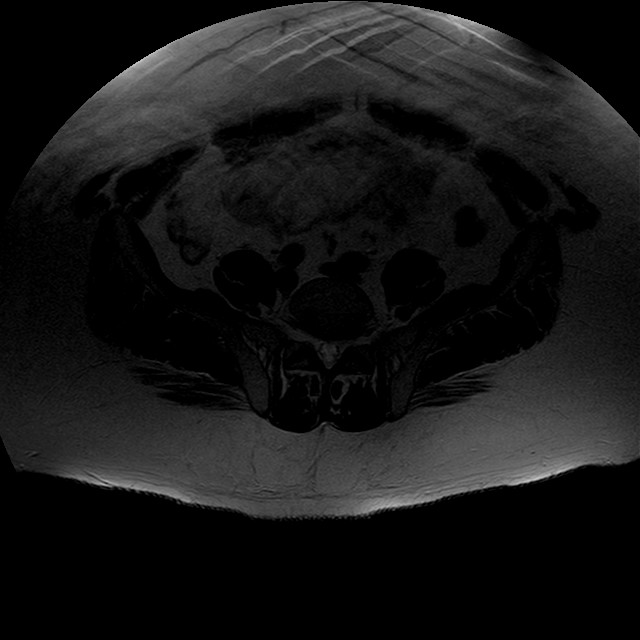

Esami: RMN BACINO

eT2w TSE

Evidenti e simmetriche alterazioni osteofitosiche in regione coxo femorale con riduzione delle rime articolari. Degenerazione completa del cercine glenoideo. Non attuali segni di versamento articolare. Non segni di edema osseo che escludono attuale algodistrofia od osteonecrosi. Lieve e simmetrica riduzione del trofismo della muscolatura glutea.